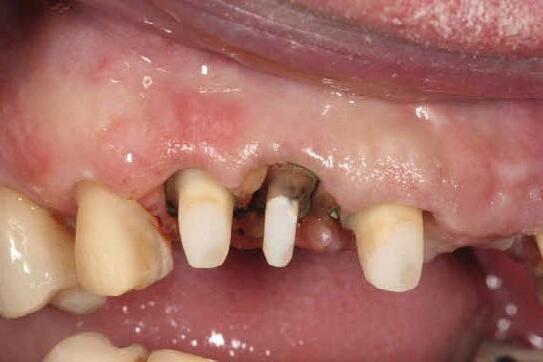

10. Titanium temporary abutments installed and composite bone graft of iPRF and MinerOss corticocancellous allograft added.

Fig 11. Bone graft filling the horizontal gap between socket and implants.

Fig 12. Screw-retained provisional restoration placed into implants, with LPRF placed to protect graft material.

Fig 13. Radiograph of implants, grafts and Provisionals.

Fig 14. Clinical view at two days post-operative visit.

Fig 15. Clinical view at two days post-operative visit